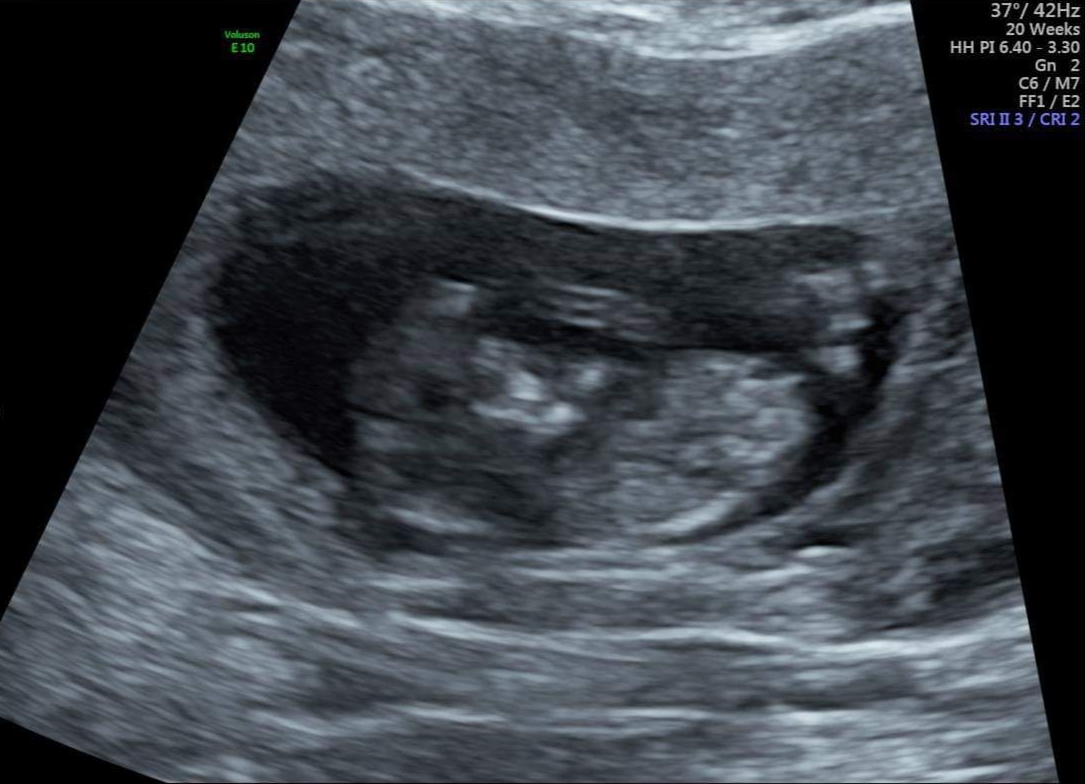

A couple from the 11 plus 4 just in case ...